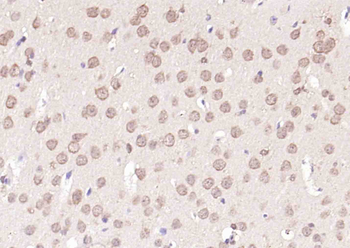

CDKN1A Antibody

Catalog Number: orb682382

| Description | CDKN1A Antibody |

| Target | CDKN1A |

200 μl, 50 μl, 100 μlCDKN1A/p21 Rabbit Polyclonal Antibody [orb11203]

FC, ICC, IF, IHC-Fr, IHC-P

Bovine, Canine, Gallus

Human, Mouse, Rat

Rabbit

Polyclonal

Unconjugated

50 μl, 100 μl, 200 μlPhospho-PAK6 (Ser560) Rabbit Polyclonal Antibody [orb6634]